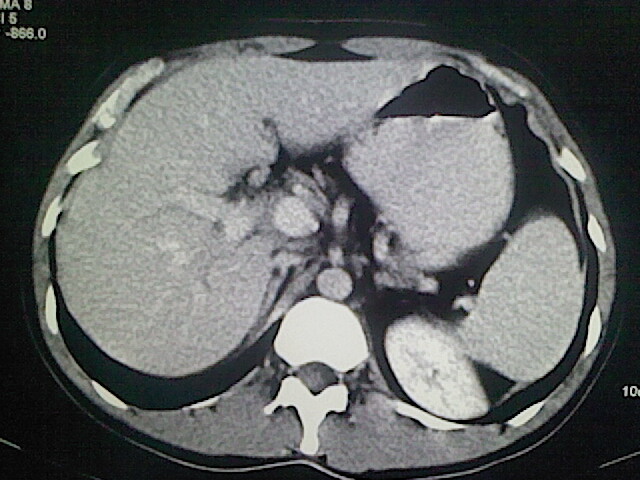

以下是引用卜一在2009-3-14 9:49:00的发言:[br]胆囊萎缩,胆囊壁不规则增厚,内部结构模糊,增强明显强化。另:肝左叶外侧段肝囊肿。支持:慢性胆囊炎!高度可疑:胆囊癌!

以下是引用余辉在2009-3-14 8:48:00的发言:[br]1)慢性胆囊炎。2)肝左叶外侧段肝囊肿。3)脂肪肝。[br]支持,胆囊萎缩,密度增高,不知b超具体有何提示,钙胆汁?结石?

以下是引用jiangjing在2009-3-14 10:18:00的发言:[br]1)慢性胆囊炎。2)肝左叶外侧段肝囊肿。3)脂肪肝。4.】建议行肝功能检查